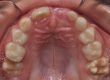

Клинични аспекти при прилагане на апарата Pendulum в смесено съзъбие

В тази статия си поставяме за цел да разискваме от клинична гледна точка позитивите и негативите при ползване на апарата Pendulum в смесено съзъбие. Ще разгледаме становищата за работа с апарата в случаите, когато са включени временните молари като опорна зона. Ще дадем какви са според нас клиничните предпоставки и индикации за използването на Pendulum в смесено съзъбие. Ще разгледаме терапевтичния протокол на няколко клинични случая, решени с прилагането на този апарат. Натрупаният от нас опит показва, че независимо кои зъби са в опорната зона се получава дистализиране на горни молари, но има разлики в не са значителни и не се отразяват негативно на основния ефект от действието на апарата Pendulum. Затова препоръчваме неговото ползване във всяка възраст и дентиция.